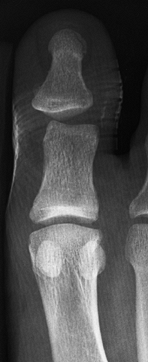

Dorsal displacement of the metatarsal head or shortening produces

transfer metatarsalgia, which can lead to significant disability (Fig. 111.10).

![]() |

Figure 111.10. Patient with persistent metatarsalgia after a “neuroma” was excised. AP (A), oblique (B), and sesamoid (C)

views show healed metatarsal fractures. The fifth metatarsal is asymptomatic; pain is due to the overload of the third metatarsal from the dorsally angulated second metatarsal. |